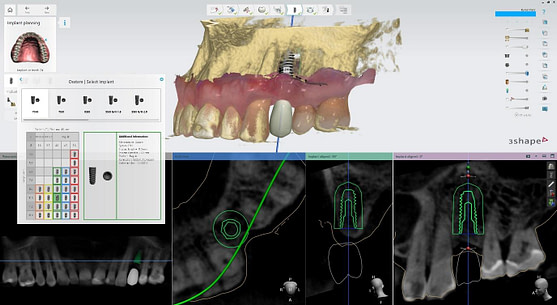

I utilized 3Shape Implant Studio, a module within the 3shape Unite Platform, to plan and execute the surgical procedure.

Pre-surgical planning began with acquiring high-quality diagnostic data, including TRIOS intraoral scans and CBCT imaging. The data was imported into 3Shape Implant Studio, where I designed a virtual crown for tooth 24 and planned the precise positioning of the implant, considering critical factors such as sinus proximity, adjacent roots, bone density, and the location of the bony defect.

A custom surgical guide was designed and 3D printed, incorporating all the critical information from the virtual planning. The implant surgery was performed under local anesthesia, with the surgical guide firmly in place to ensure accurate implant placement. Bone grafting was performed to address the bony defect and promote optimal healing.

The Osstem OneGuide kit is used with a fully guided osteotomy and implant placement.

Osstem TSIII D4 x H10mm implant on NoMount driver.